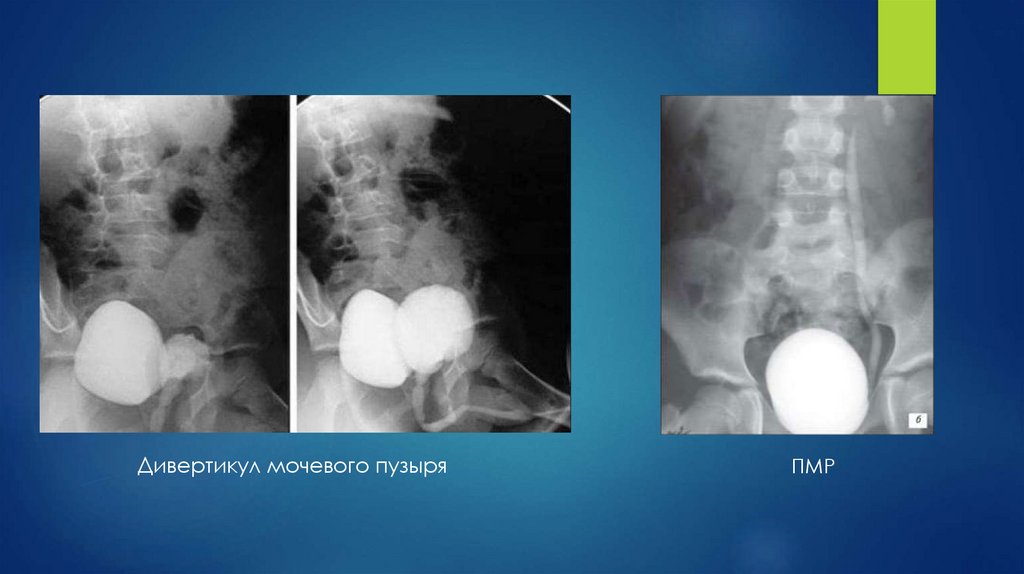

53.

Дивертикул мочевого пузыря

ПМР